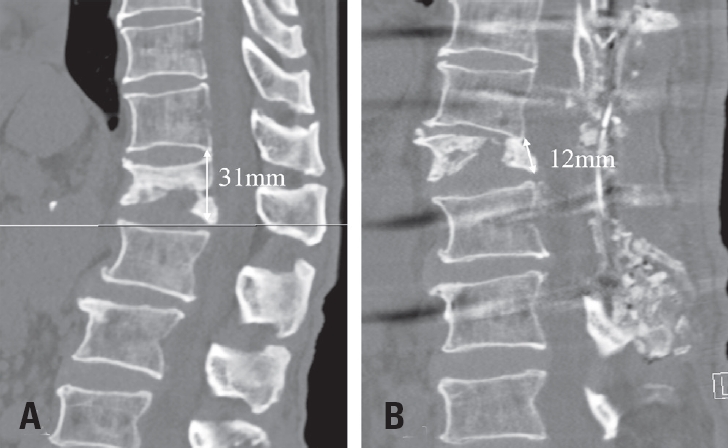

Fig. 3.

Preoperative and postoperative measurements of the L1 vertebral body. (A) The preoperative posterior height of the L1 vertebral body was approximately 31 mm. (B) Postoperatively, the height was reduced to 12 mm, indicating that a total spinal shortening of approximately 19 mm was achieved via the spinal shortening osteotomy.

Fig. 3. Preoperative and postoperative measurements of the L1 vertebral body. (A) The preoperative posterior height of the L1 vertebral body was approximately 31 mm. (B) Postoperatively, the height was reduced to 12 mm, indicating that a total spinal shortening of approximately 19 mm was achieved via the spinal shortening osteotomy.

An osteotomy was performed on the L1 vertebral body parallel to the T12 lower endplate. A temporary rod was placed, and under strict IONM surveillance, the spinal column was gradually shortened by compressing the pedicle screws (Fig. 2). This maneuver brought the T12 lower endplate into contact with the osteotomized surface of the L1 body. Approximately 20 mm of shortening was achieved. Permanent rods were secured, and posterolateral fusion was performed using local autograft (Fig. 3).